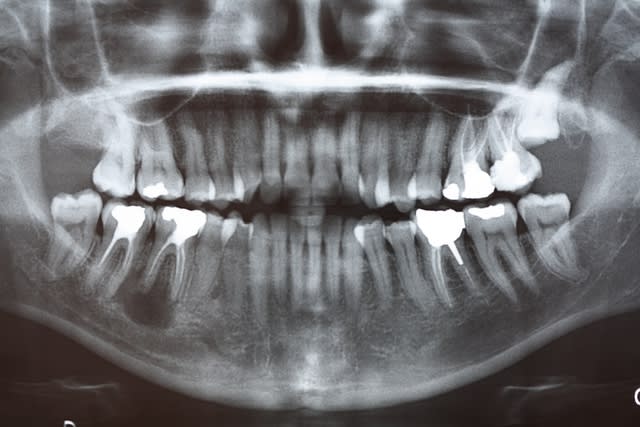

Que côte-t-on quand on extrait 28-38-48-47-46 avec curetage du kyste..?

DC30 pour le curetage du kyste étendu aux apex de deux dents et nécessitant trépanation osseuse, (extraction des dents comprises), puis DC16 + 16/2 + 16/2 pour les extractions simples.

reprise endo de 46 47 26 27 extraction 28 (pourquoi faire?

le tout chez l'endodontiste si après un cone beam il est optimiste pour 46

CURETAGE KYSTE et exo de 46 mais pourquoi enlever le reste ?si la 28 ne pose pas de pbl il faut la laisser là ou elle est!!!! et si 47 est vitale (test au froid siffit) il faut limiter les degats au maximum!!!!soyez conservateurs!!!!

oups 47 a voir au moment mais au pire exo 46/47 chez stomato

Le curetage de kyste DC30 est si tu pratiques une trépanation osseuse sinon c'est DC15 pour "kyste de petit volume par voie alvéolaire élargie" + l'extrac' normale.

Donc dans ton cas :

DC40 pour 25,

DC16 pour 46 et DC24 pour le kyste,

Et la cotation habituelle DC16,8 ou 10 (alvéo) si tu extraies dans la même séance ou non.

Sinon sur le plan clinique, perso j'essaie le RTE (en NR évidemment) sur 46, je n'extraie 28 que si elle commence à s'annoncer en bouche, 38 et 48 si elles ne sont pas calées par 17 et 27 comme ça semble être être le cas.